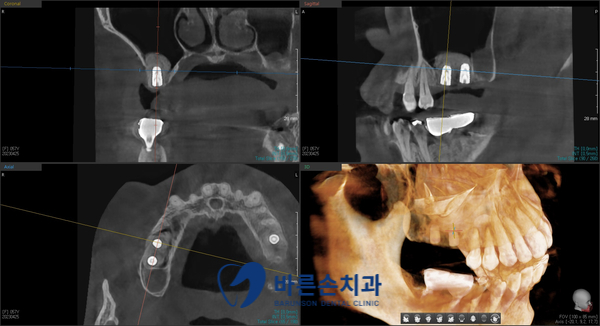

파노라마 엑스레이 촬영 후, 치료 계획을 세웁니다.

X 표 치아들은 발치하고, 임플란트를 하기로 계획합니다.

상악동 함기화(노란선)로 인해, 상악동 공간에 뼈가 많이 부족하고,

치은연하(잇몸 밑으로 내려간) 치석으로 인해 치주염이 심합니다.

위 어금니들은 임플란트와 상악동 측방 거상술로 뼈 이식을 많이 해서 기다리는 중이고,